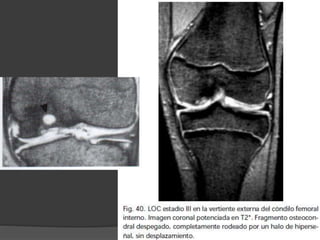

Osteocondritis disecante

 lesión osteocondral originada por traumatismo (50%)

 Mas frecuente niños y adolescentes, en los que el cartílago

articular es más resistente que el hueso subcondral.

 1 y 2 no hay

cambios

artroscópicos

II

IV